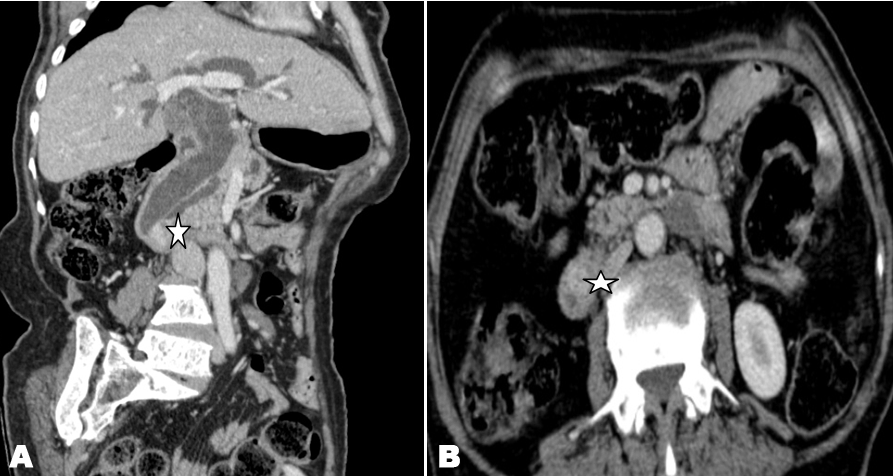

Malignant melanoma are tumors that derived from melanocytes. Malignancy will grow irregularly and then might function made abnormally. Melanoma will produce pigment in varying number and can elicit immune response of the body. When the immune response decreased might function made clinical appearance would worsen (Figure 1, Figure 2).

Figure 1: (A and B): Clinical picture of melanoma maligna of the left calcaneal region in patient male, 72-years-Old.